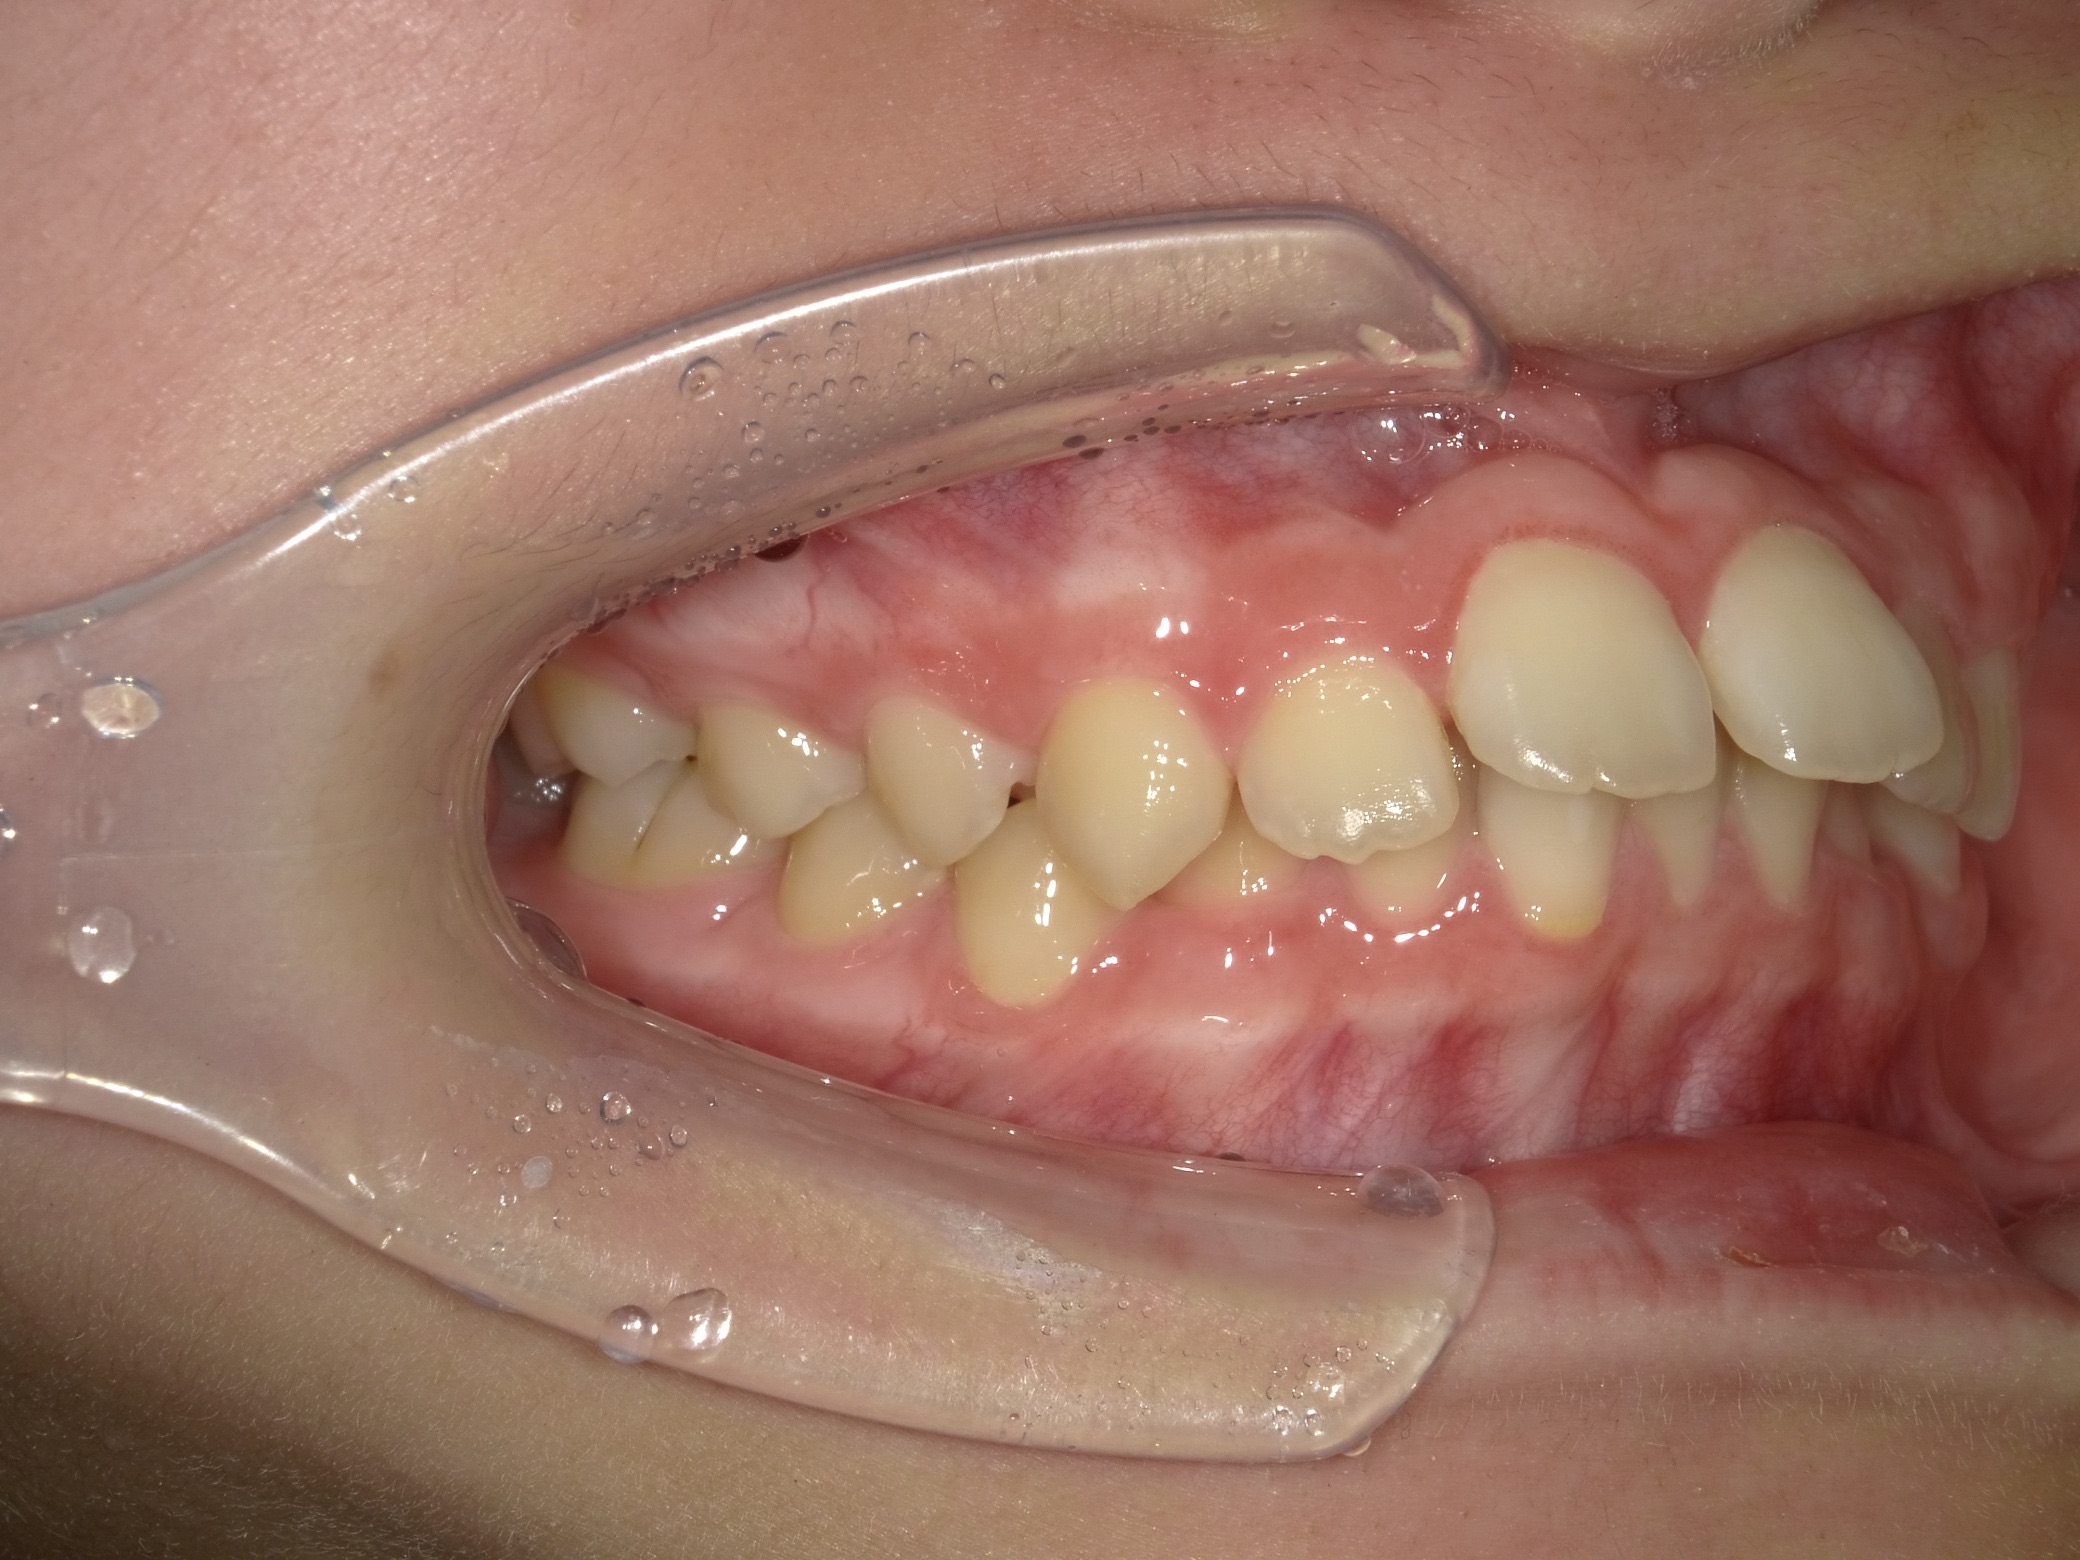

1年4カ月で前歯が出ていること、隙間があることを改善したケース

マウスピース矯正インビザライン単独による非抜歯矯正治療を実施。

隙間を閉じ上の歯を下げるようにマウスピース矯正で治療を行いました。

主訴

前歯にすき間がある上に出っ張っているのを治したい